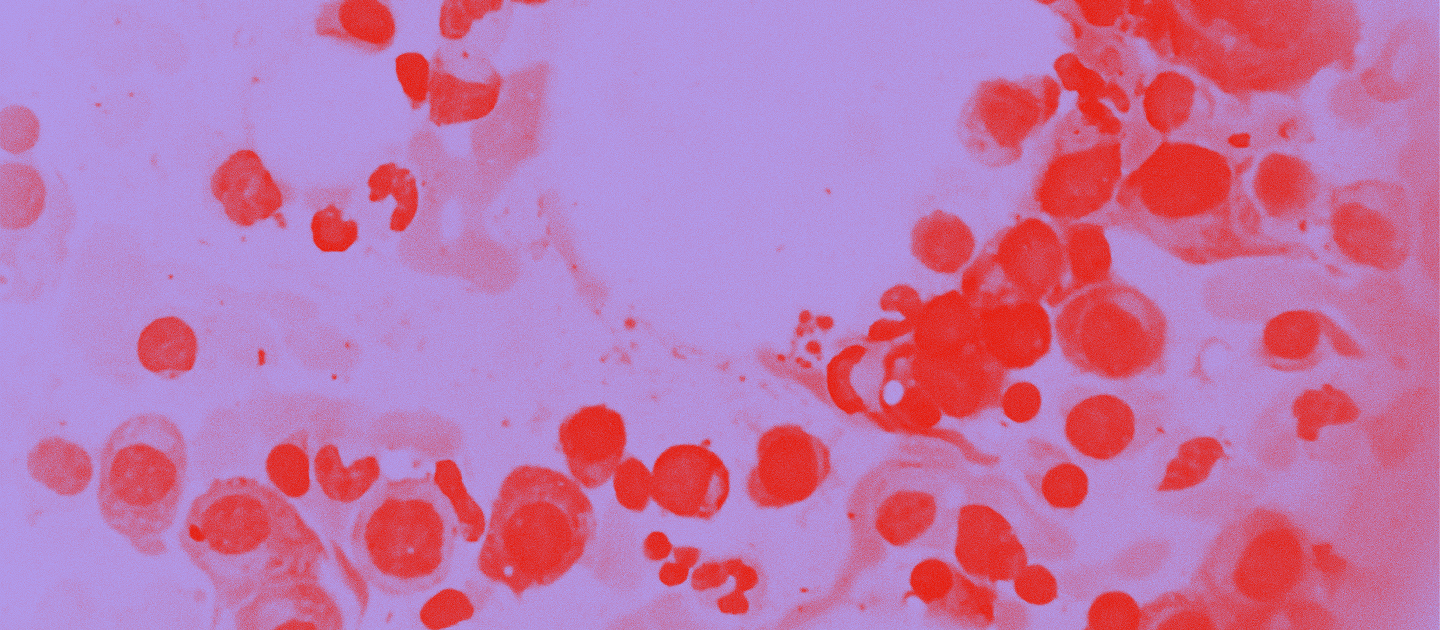

Multippeli myelooma on veren plasmasolujen toimintaan liittyvä syöpäsairaus, jossa pahanlaatuiset plasmasolut vahingoittavat luuytimen normaalia verenmuodostusta. Usein hitaasti etenevässä sairaudessa pahanlaatuiset plasmasolut valtaavat lopulta luuytimen ja aiheuttavat syöpymäpesäkkeitä luustoon.1

Luuydinnäyte on keskeinen osa diagnostiikkaa, sillä verisolujen muodostus tapahtuu luuytimessä, ja näytteestä voi ilmetä mahdolliset poikkeamat luuytimen toiminnassa. Myeloomalle tyypillinen lisääntynyt plasmasolujen määrä näkyy nimenomaan luuytimessä, ja samalla monella sairastuneista normaalien verisolujen tuotanto vähenee.1